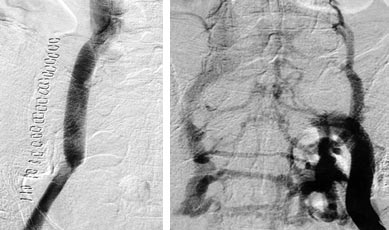

| Fig. 3 |

Postoperative venography showed a patent ePTFE

graft (A), and a good venous drainage from the left-side iliac

veins (B). |